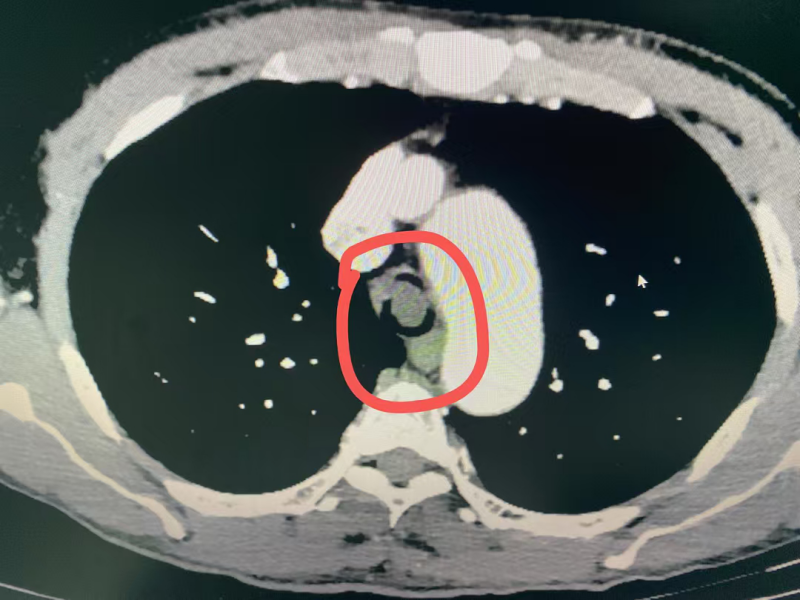

同样呼吸困难的情况也发生在54岁的黄先生身上,黄先生因食管癌晚期,在外院经多次放疗和化疗后疾病仍进展,春节期间突发明显呼吸困难至当地医院就诊,当地医院完善肺部CT后发现黄先生的食管肿瘤已严重压迫气管,气道呈现“一线天”改变,最狭窄处仅剩余5mm不到。